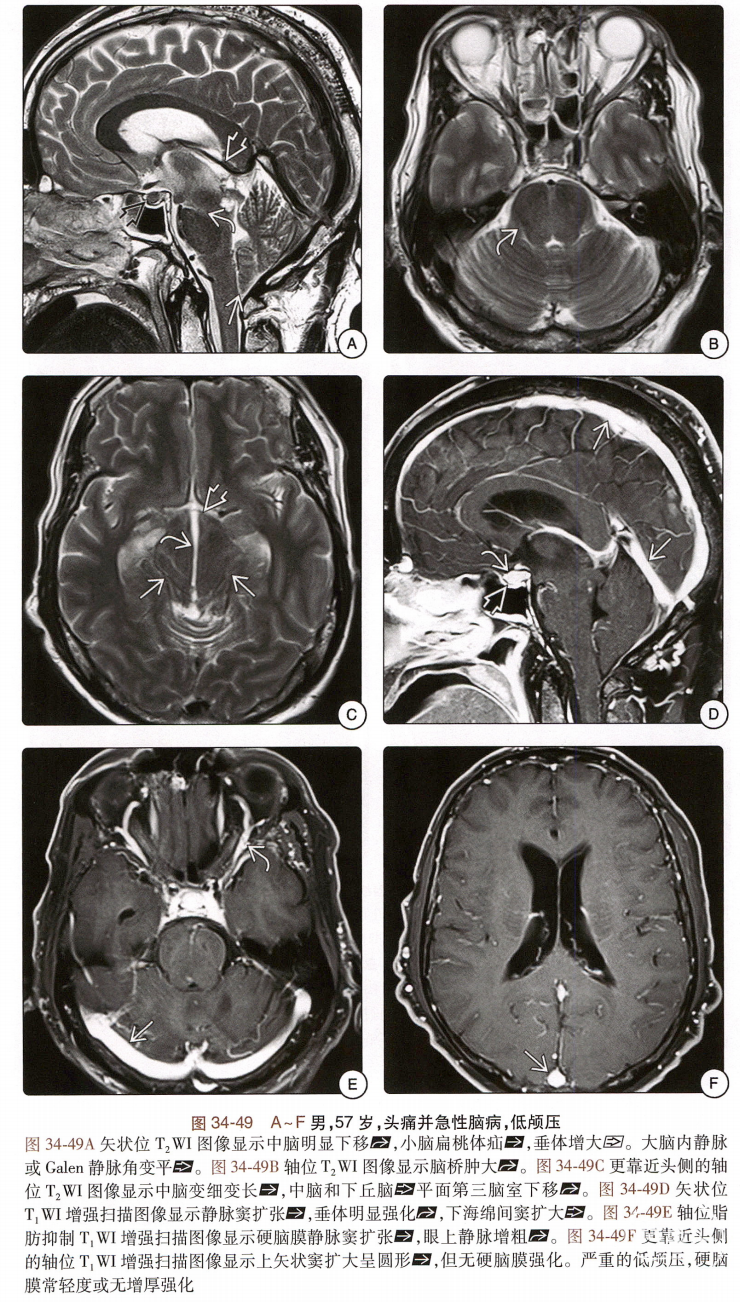

低颅压综合征